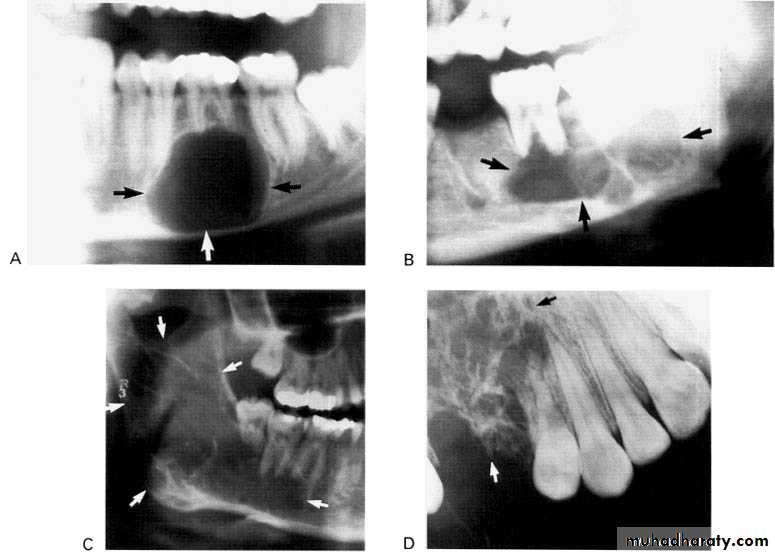

*A 55 year old man with an expansile multilocular radiolucency of the left mandible. The swelling had been noticed by the patient for approximately one year.

A: Odontogenic fibroma

B,C,D:Odontogenic myxoma.Odontogenic Adenomatoid Tumor (OAT)

Central giant cell granuloma*A relatively uncommon, non- neoplastic mass in the jaws (intraosseous) producing an expansile radiolucent soap bubble appearance.

Multilocular appearance, expansion (arrowed) and considerable displacement of the adjacent teeth.

Buccal and lingual expansion (arrowed) and the undulating cortical border.

Large multilocular aneurysmal bone cyst

in the ramus with marked expansion andthe displacement of/8.